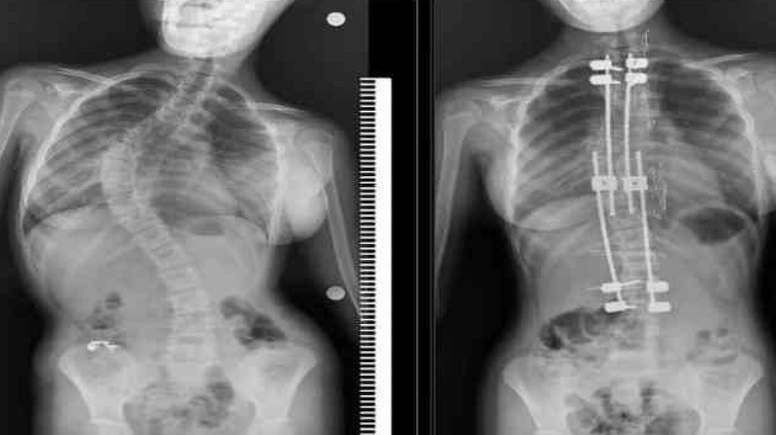

Skolyozlu çocuklar için doğru tedaviyle normal yaşam mümkün